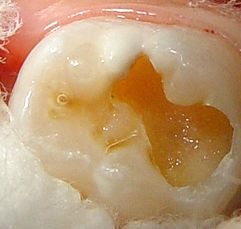

Caso clínico

Paciente niño, sexo masculino, 5 años de edad

Figura 15: Diagnóstico.

Figura 16: Cavidad (Papacarie)

Figura 17:

Remoción de tejido infectado- movimientos laterales.

Reaplicación del gel y nuevo raspado

Constatación de transparencia del gel (aspecto vítreo)

Figura 18: Limpieza cavitaria

Figura 19: Preparación del cemento de Vidrio Ionómero y su inmediata inserción. Digitopresión

Terminación de la reconstrucción.

Control oclusal.

Protección con barniz.